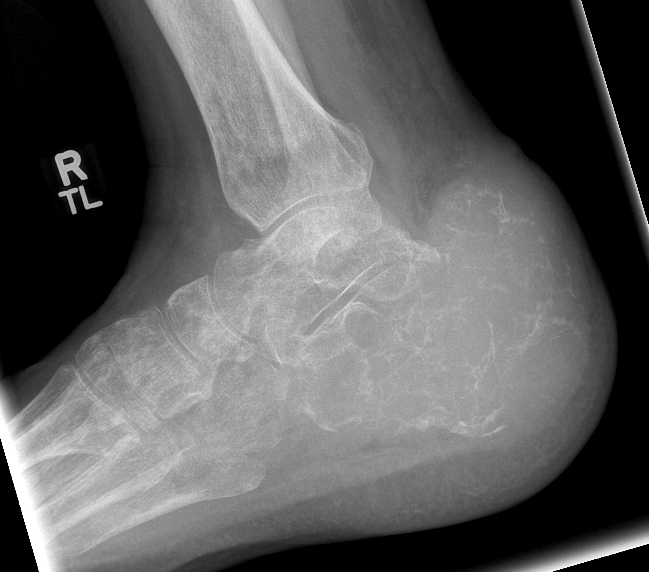

Giant cell tumour

Painful swollen foot / ankle

Lytic area on X-ray

Calcaneus > talus

Curettage and bone grafting